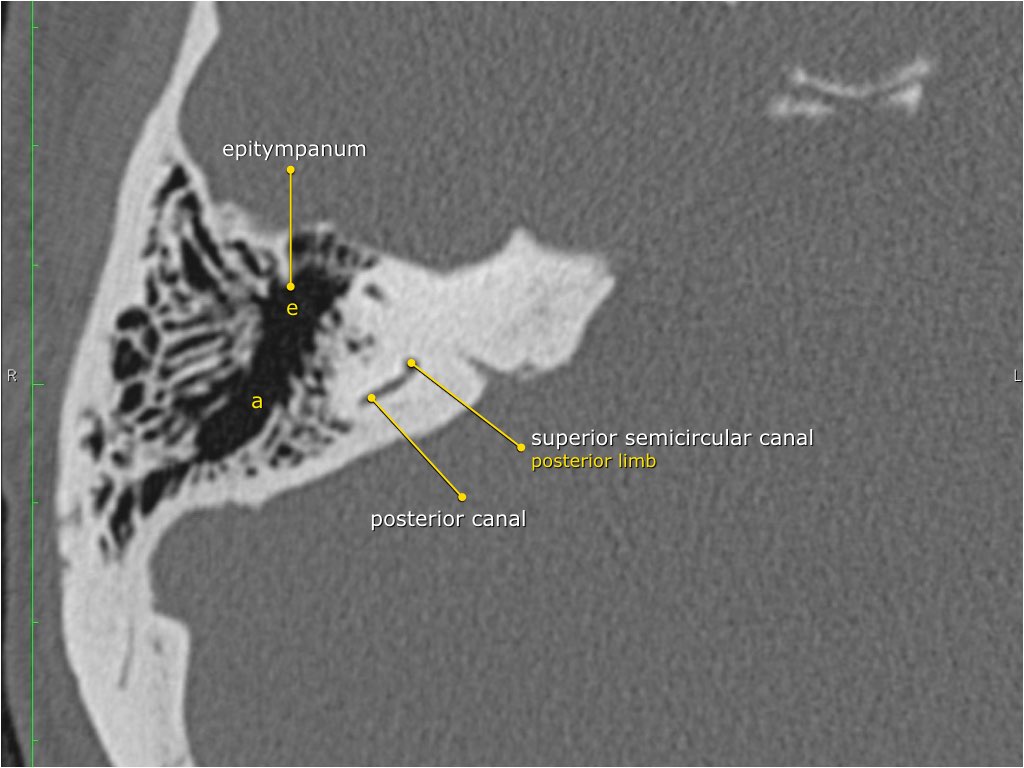

Giải phẫu mặt phẳng coronal của xương đá

Nhấp vào hình ảnh để phóng to.

Cuộn qua các hình ảnh.

Hang bào chũm (Antrum)

Hang bào chũm là một tế bào khí lớn nằm phía trên và phía sau hòm nhĩ, thông với hòm nhĩ qua ngách hang (aditus ad antrum).

Hang bào chũm được bao quanh bởi các tế bào khí chũm nhỏ hơn.